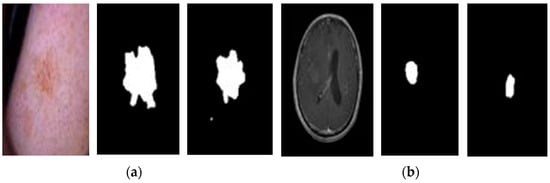

3.3. Data Segmentation

- Skin Lesions: In skin lesion images, hair and surrounding healthy skin can introduce noise, making it difficult for the model to distinguish the lesion itself. The model may focus on irrelevant features instead of the lesion characteristics that are crucial for accurate classification.

- Brain Tumors: Similarly, in brain MRI scans, the model may be overwhelmed by information from healthy brain tissue rather than focusing solely on the tumor region. This can negatively influence the model’s ability to segment the tumor accurately.

4.2. Feature Extraction and Cancer Type Classification with U-Net

- U-Net Segmentation (described in Section 3.3): a U-Net architecture is employed to extract informative features from the preprocessed images. This segmentation step focuses on identifying the region of interest (ROI) within the image, which contains the potential cancerous tissue (skin lesion or brain tumor). This targeted approach allows the model to concentrate on the most relevant image area for classification. The segmentation results for sample images are illustrated in Figure 7, demonstrating the U-Net’s ability to identify potential problem regions.